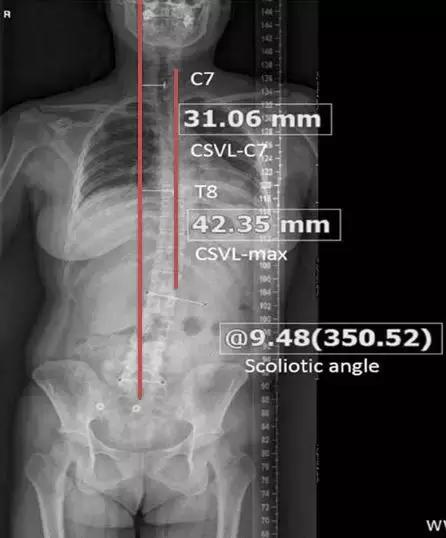

怎么判断自己有没有侧弯呢?

大多数患者是在照镜子的时候发现不对劲的。如果镜子里从正面看,自己的双侧肩膀左右不等高,提示有可能出现脊柱侧弯了。

这时候可以让家人从后方观察,如果后背左右不平,后背中线左右扭曲(如下图左图),就应高度怀疑脊柱侧弯。

随后应该到医院拍摄全脊柱X线片(如下图右图)进行确诊,同时由专业医生进行测量,了解侧弯的幅度,如果成角超过10度,就可以诊断为脊柱侧弯了。

此外从影像上,还可以看出腰椎侧弯后,上半身重心的偏移情况。

如下图所示,患者的头部相对于臀部,朝着图中右侧的方向移位了。这个移位超过1cm就可以诊断为上半身重心偏移。